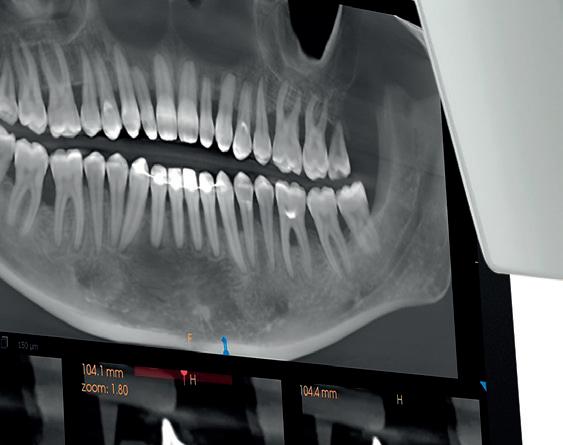

VistaScan Mini View 2.0 from Dürr Dental is compact and easy to use. The simplicity of the scanning process is matched by exceptional image clarity.

Anything else is a compromise.

For more information visit www.duerrdental.com/en/products/imaging/